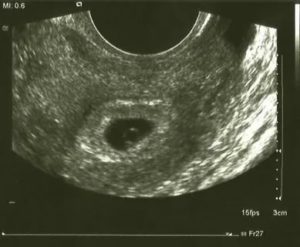

Аппарат УЗИ с высоким разрешением способен определить беременность на 5-6 день задержки месячных (это соответствует 3 неделям вынашивания плода). Ультразвуковое исследование на этом сроке фиксирует в полости матки крохотный бугорок размером 2-4 миллиметра. Это и есть растущий зародыш.

Определить, что это: складки эндометрия или растущий зародыш, под силу только специалисту высокой квалификации.

Современная трансвагинальная ультразвуковая диагностика позволяет увидеть плодное яйцо в маточной полости на 3 неделе. На 4 неделе в яйце уже виден зародыш.

В начале четвертой недели наступает то время, когда видно плодное яйцо на УЗИ. Правда, оно имеет совсем небольшой размер, всего 1 мм диаметром, зато обладает огромным потенциалом. При таком размере рассмотреть, как происходит развитие будущего ребеночка, никак нельзя, потому что размер эмбриона слишком мал.